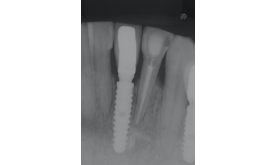

Foi instalado um implante Due Cone de 3.5 x 13.0 mm, que foi estabilizado a 45 Ncm, e uma prótese provisória adesiva, instalada para permanecer durante as 12 semanas de espera para o segundo tempo cirúrgico (Figuras 11 e 12).

Após esse período, foi selecionado o pilar, e um Pilar Ideale reto de 3.3 X 4.0 X 1.5 mm foi instalado e torqueado a 20 Ncm (Figuras 13 e 14).